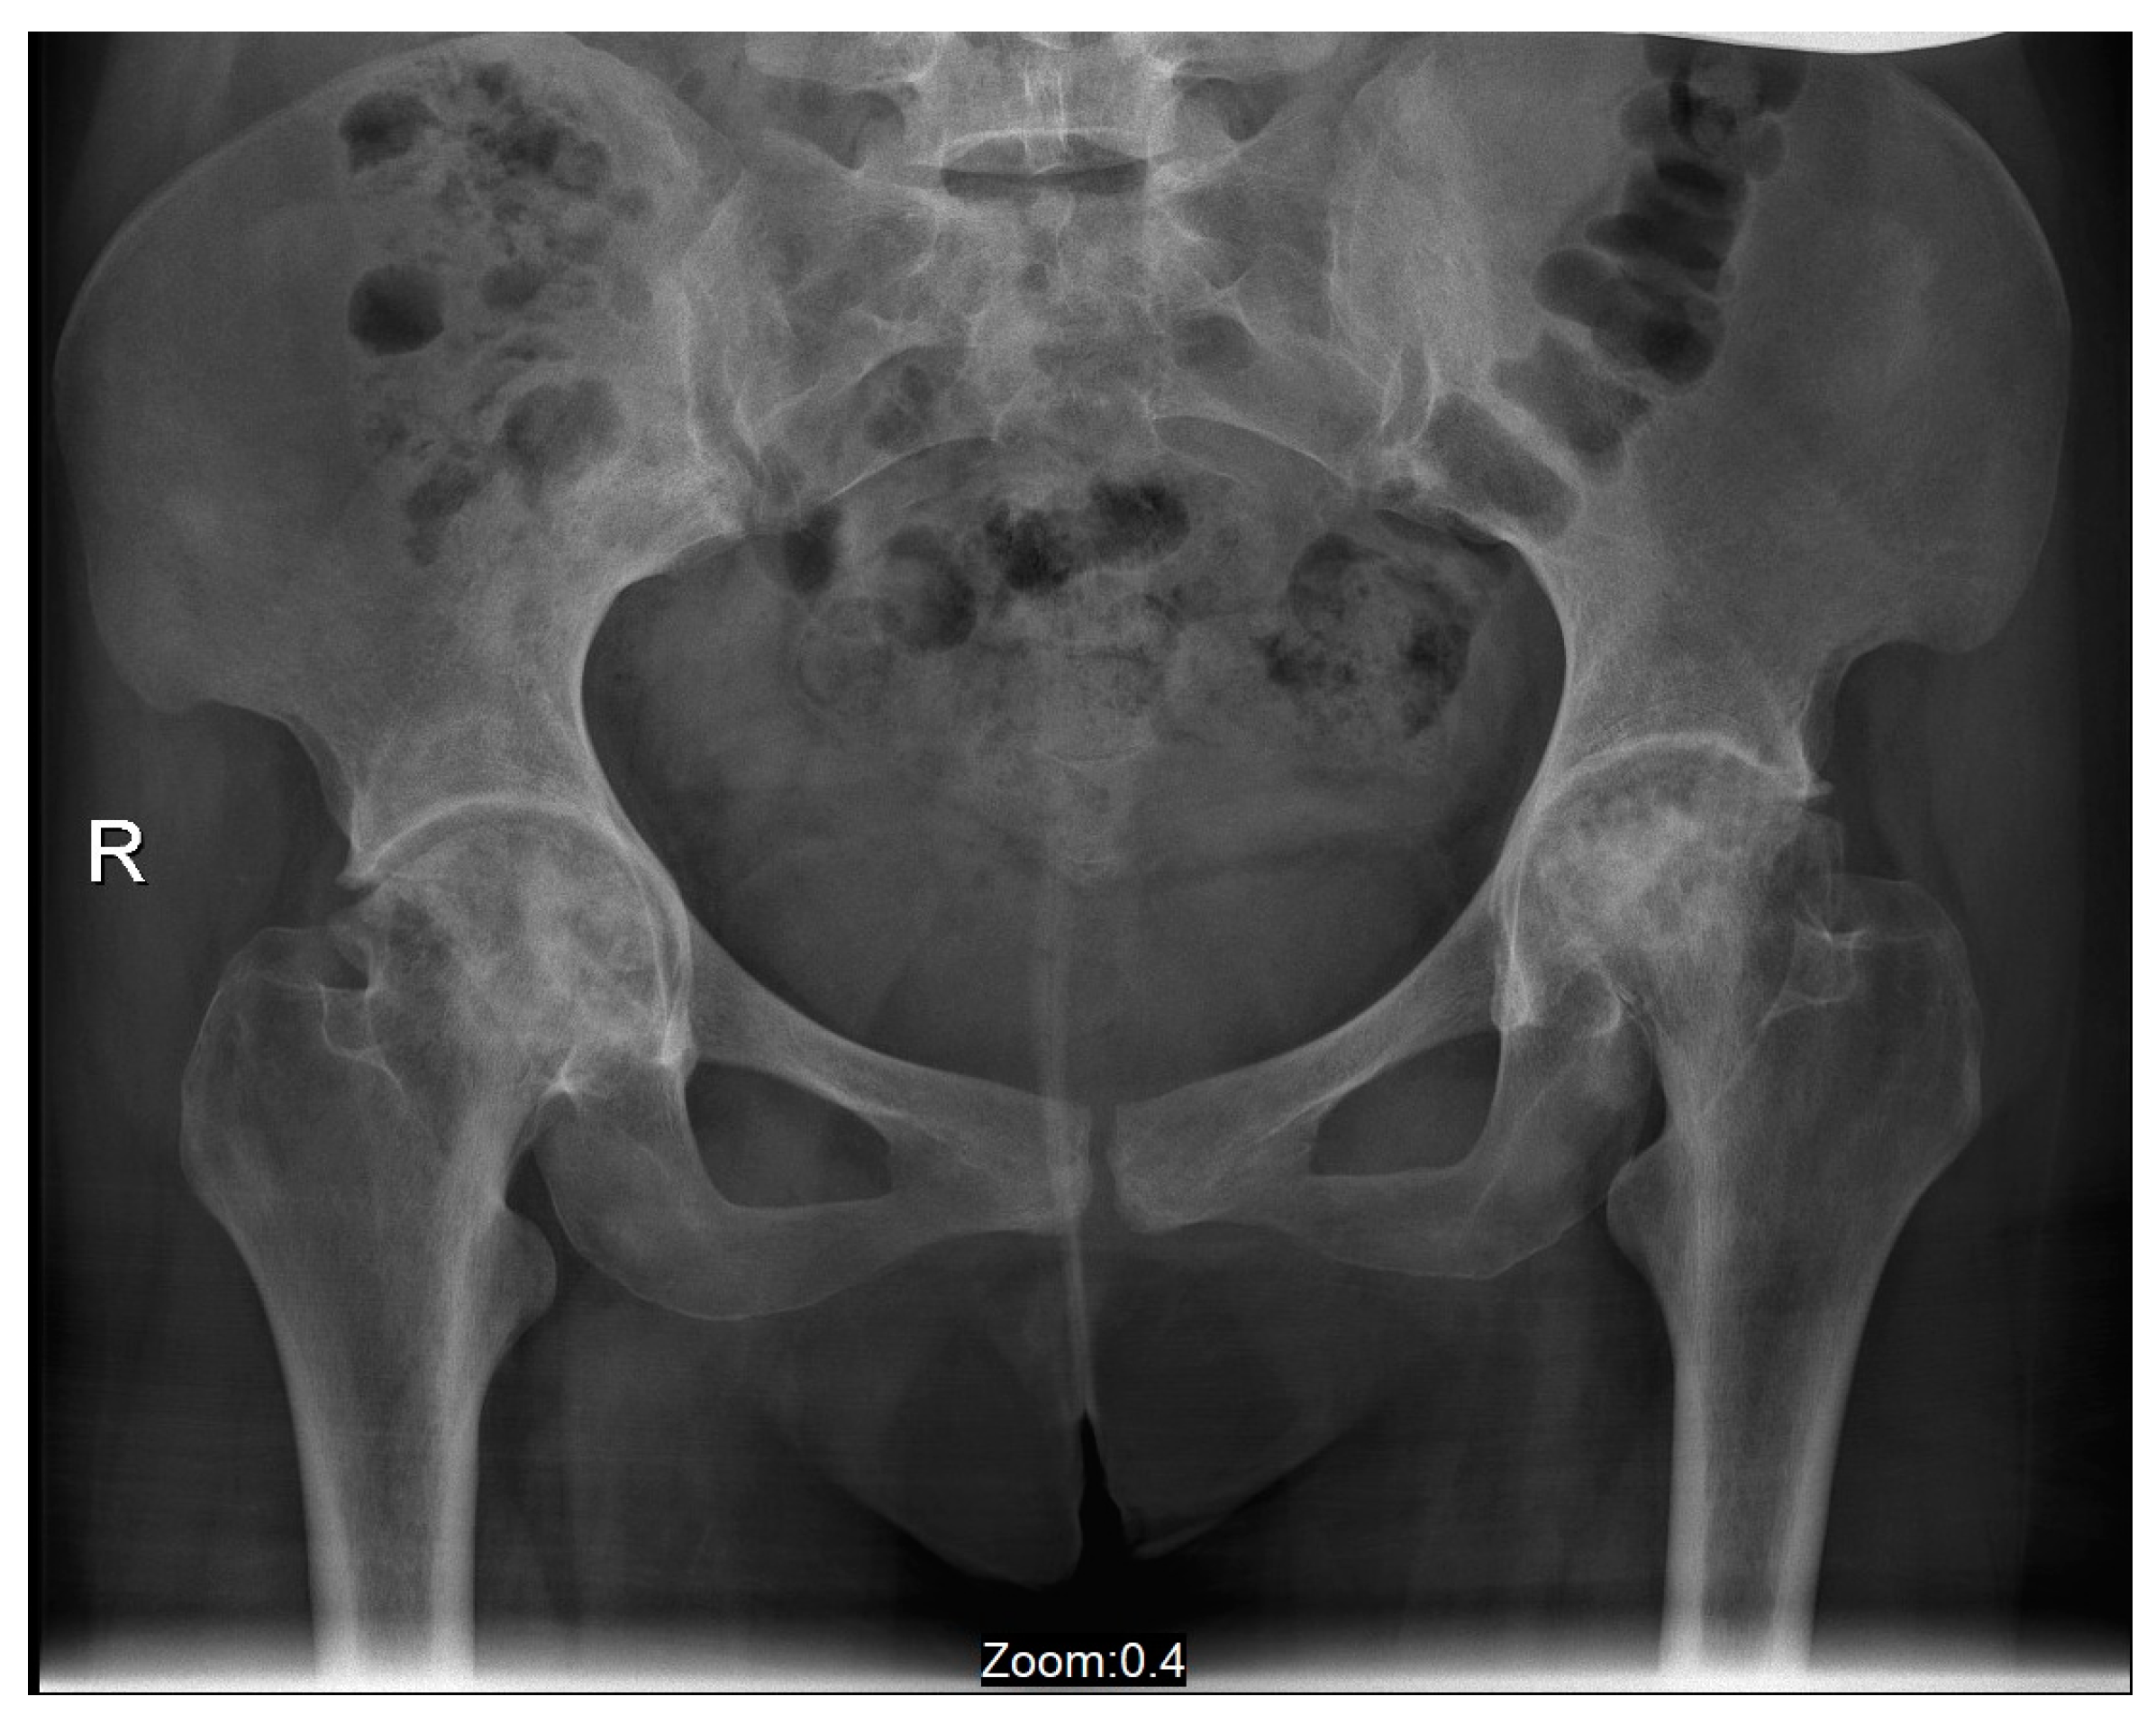

Figure 2.

An antero-posterior X-ray of pelvis and hip joints of Case 1 performed four years after the acute events. These findings present severe bilateral osteoarthritis.